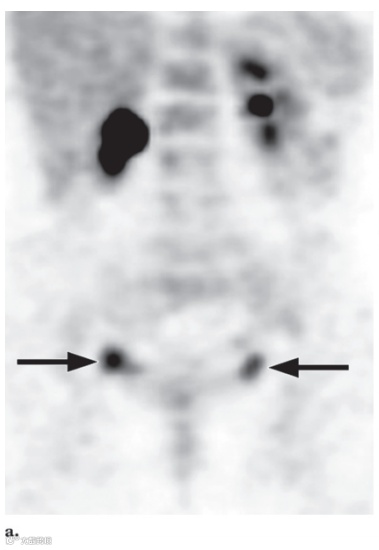

图12. 一名15岁女孩的良性卵巢18F FDG 摄取,该女孩有腹部大B细胞淋巴瘤病史。

冠状18F FDG PET 扫描 (a) 和轴位融合PET/CT图像 (b) 显示双侧卵巢FDG摄取增高灶 (箭头),与月经中期排卵有关。随访成像显示摄取增高灶消退。